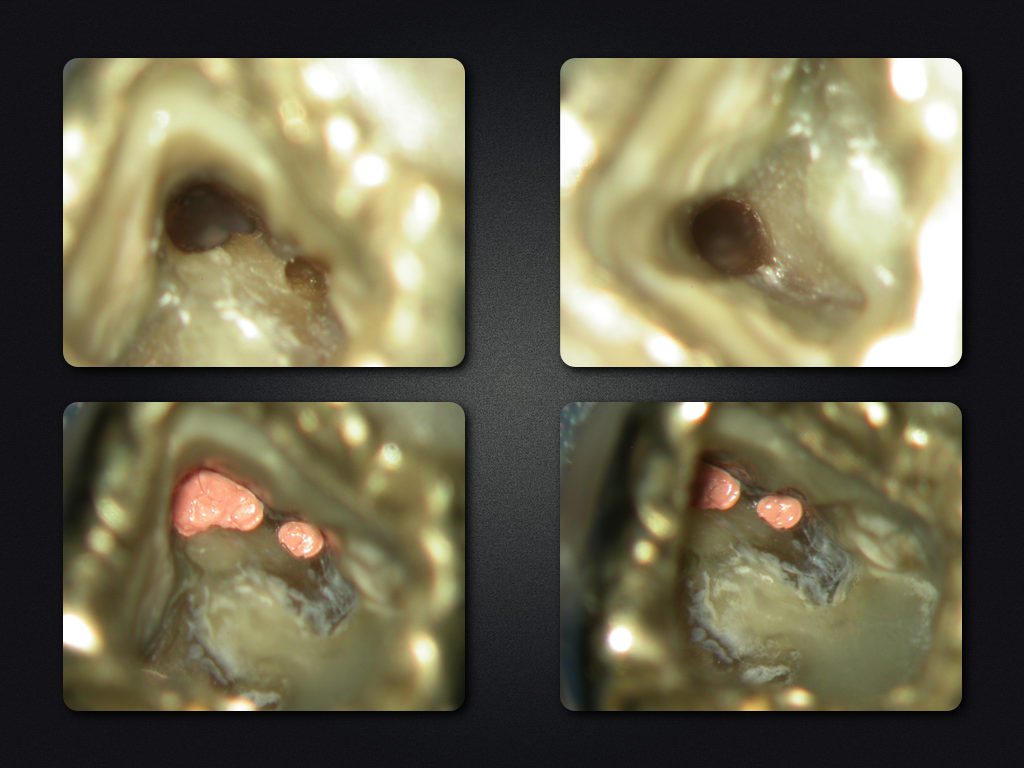

2D vs. 3D (XXV)